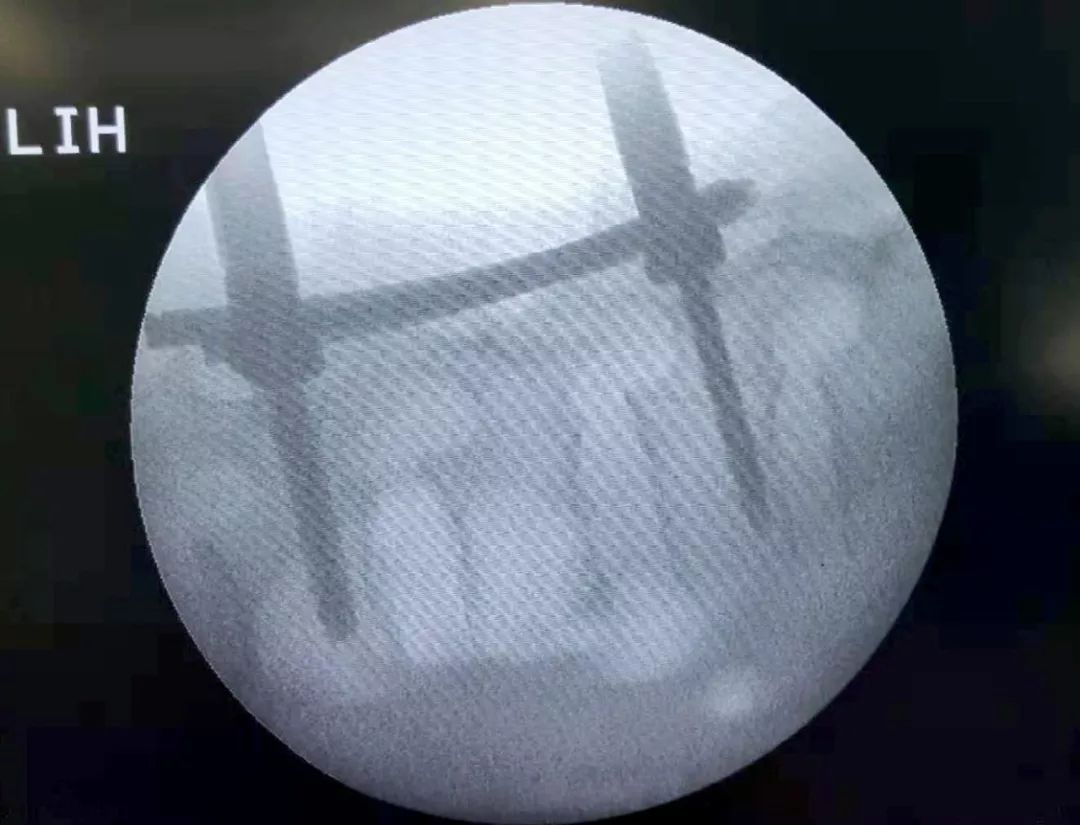

正位示椎弓根螺钉位置

侧位示椎弓根螺钉位置